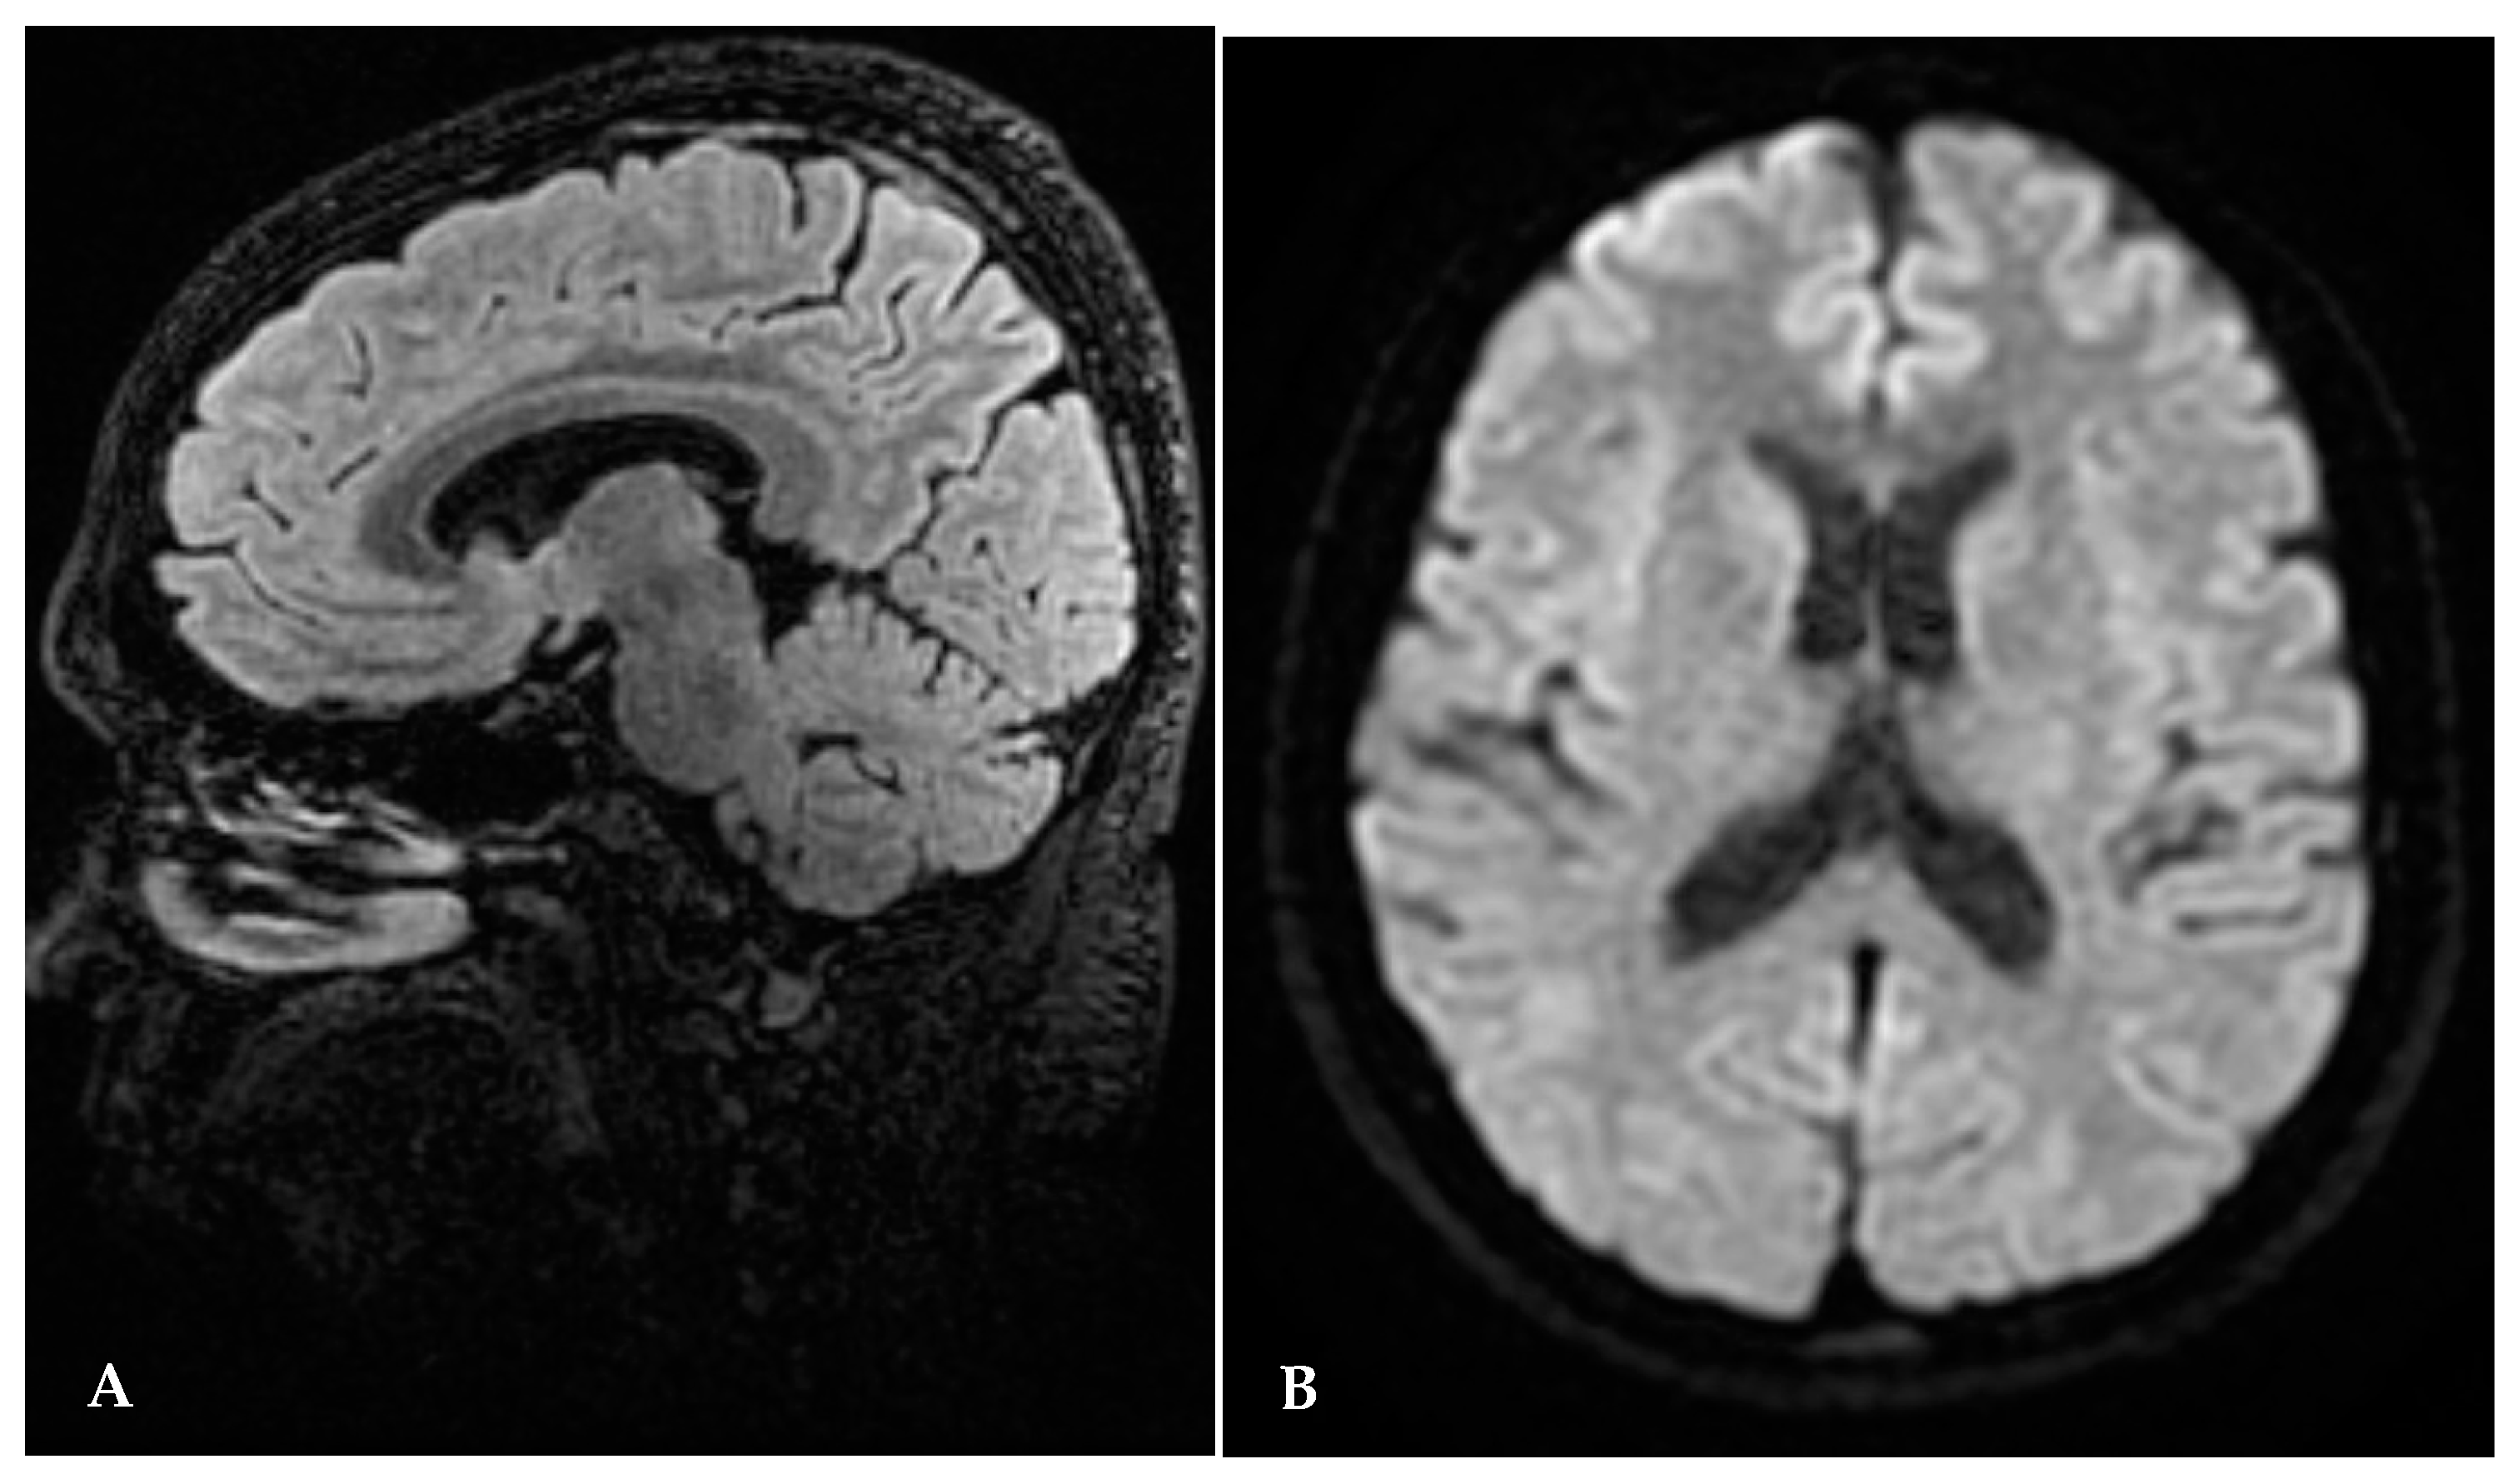

A second brain MRI, performed seven months after the beginning of thiamine replacement and one month after delivery, showed hyperintensity to have completely disappeared in the splenium of corpus callosum in thalamic and periaqueductal areas (Figure 2A,B).

Figure 2.

(A,B) Brain MRI seven months after thiamine start: disappearance of abnormal signal.